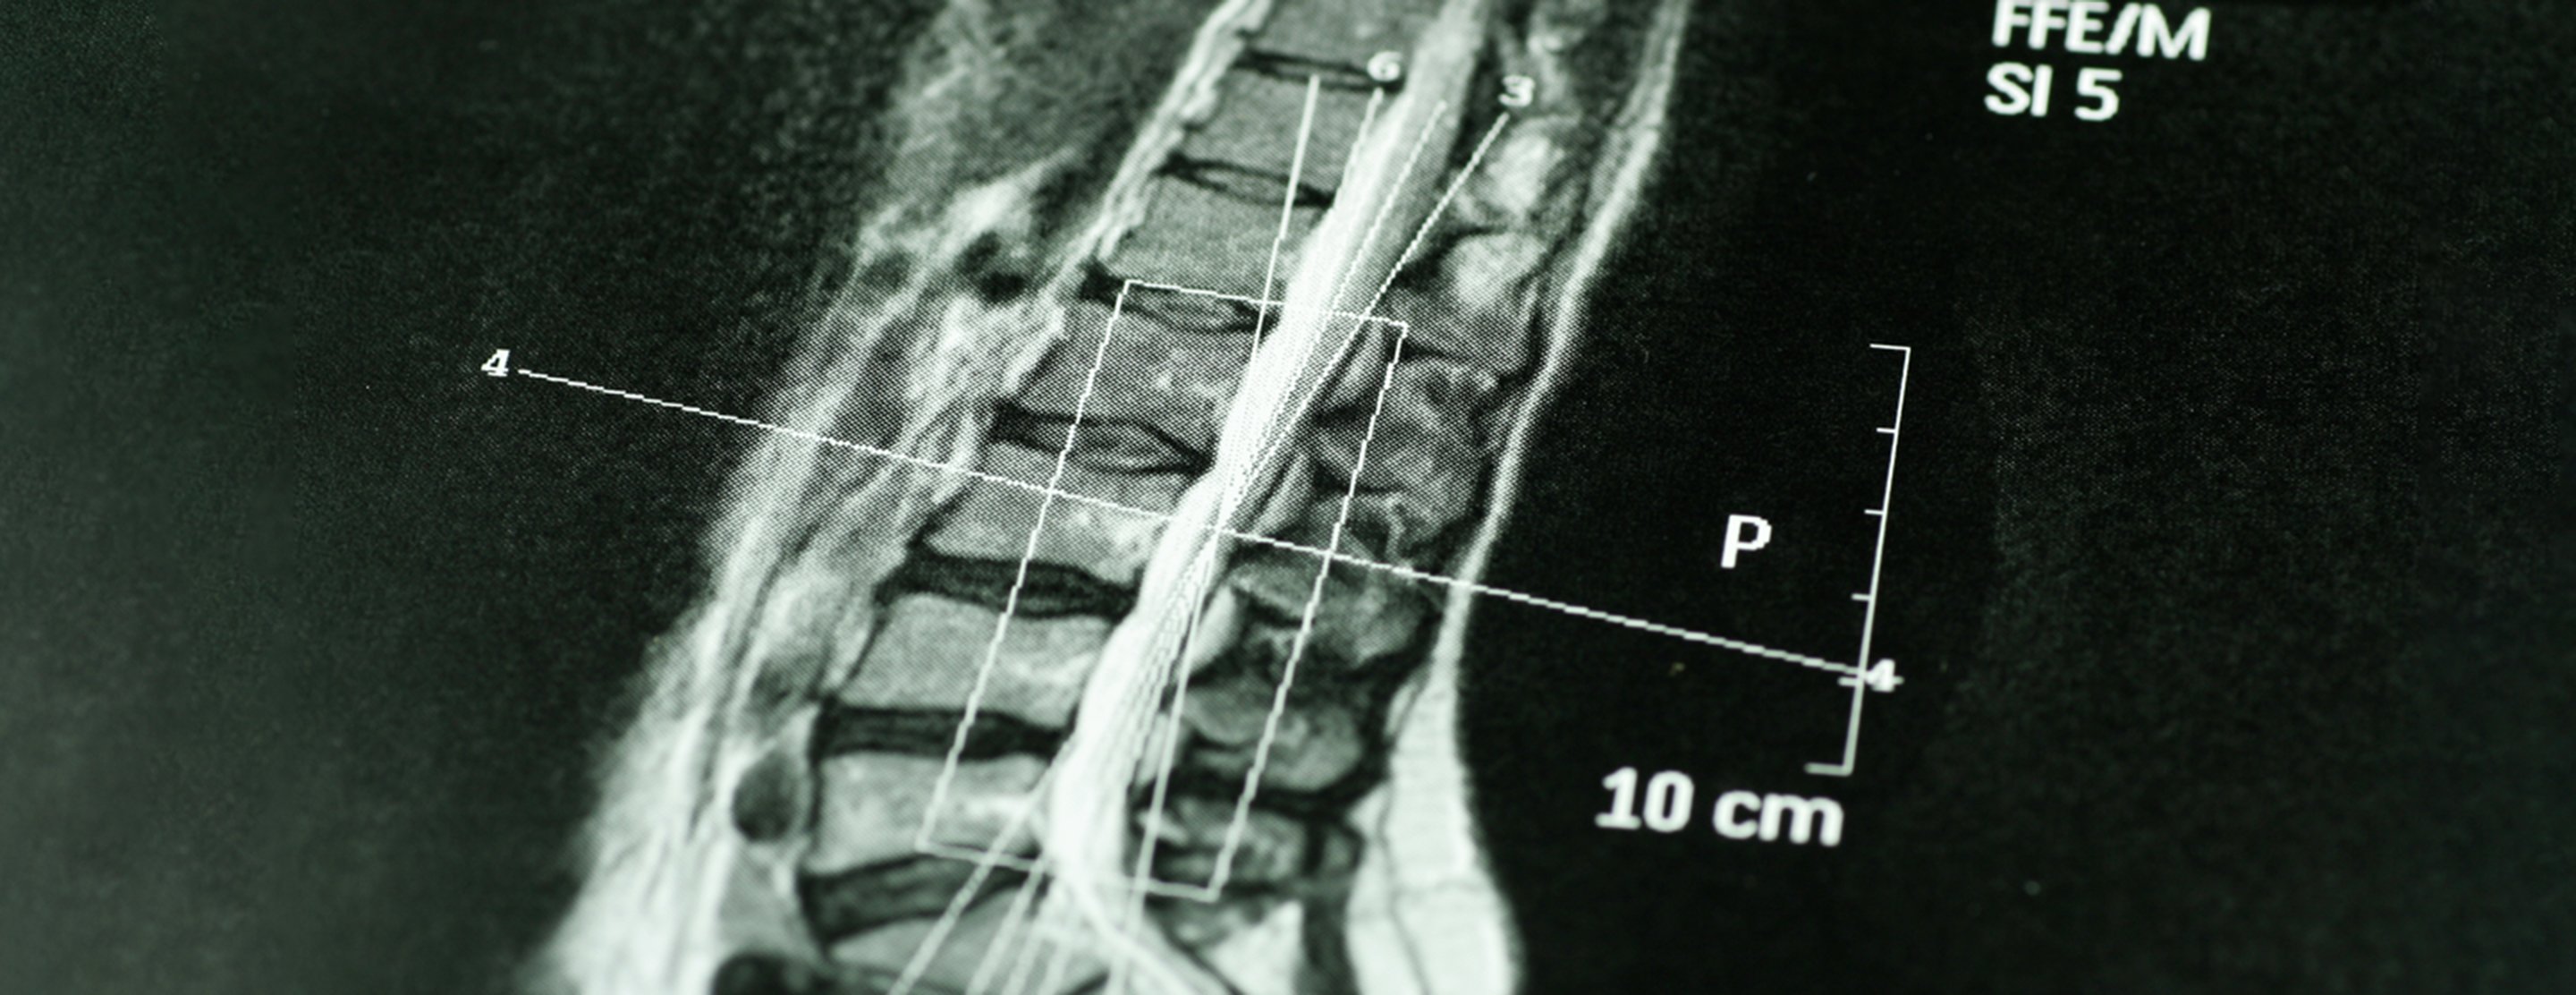

Thoracic spine CT scan

A computed tomography (CT) scan of the thoracic spine is an imaging method. This uses x-rays to rapidly create detailed pictures of the middle back (thoracic spine).

A computer creates separate images of the body area. These are called slices. These images can be stored, viewed on a monitor, or printed on film. The slices together can create three-dimensional models of the body area.

CT rapidly creates detailed pictures of the thoracic spine. The test may help diagnose or detect:

The thoracic CT scan is good for evaluating large herniated disks. It can miss the smaller ones. This test with a myelogram will show a better image of the nerve roots and find smaller injuries or abnormalities.